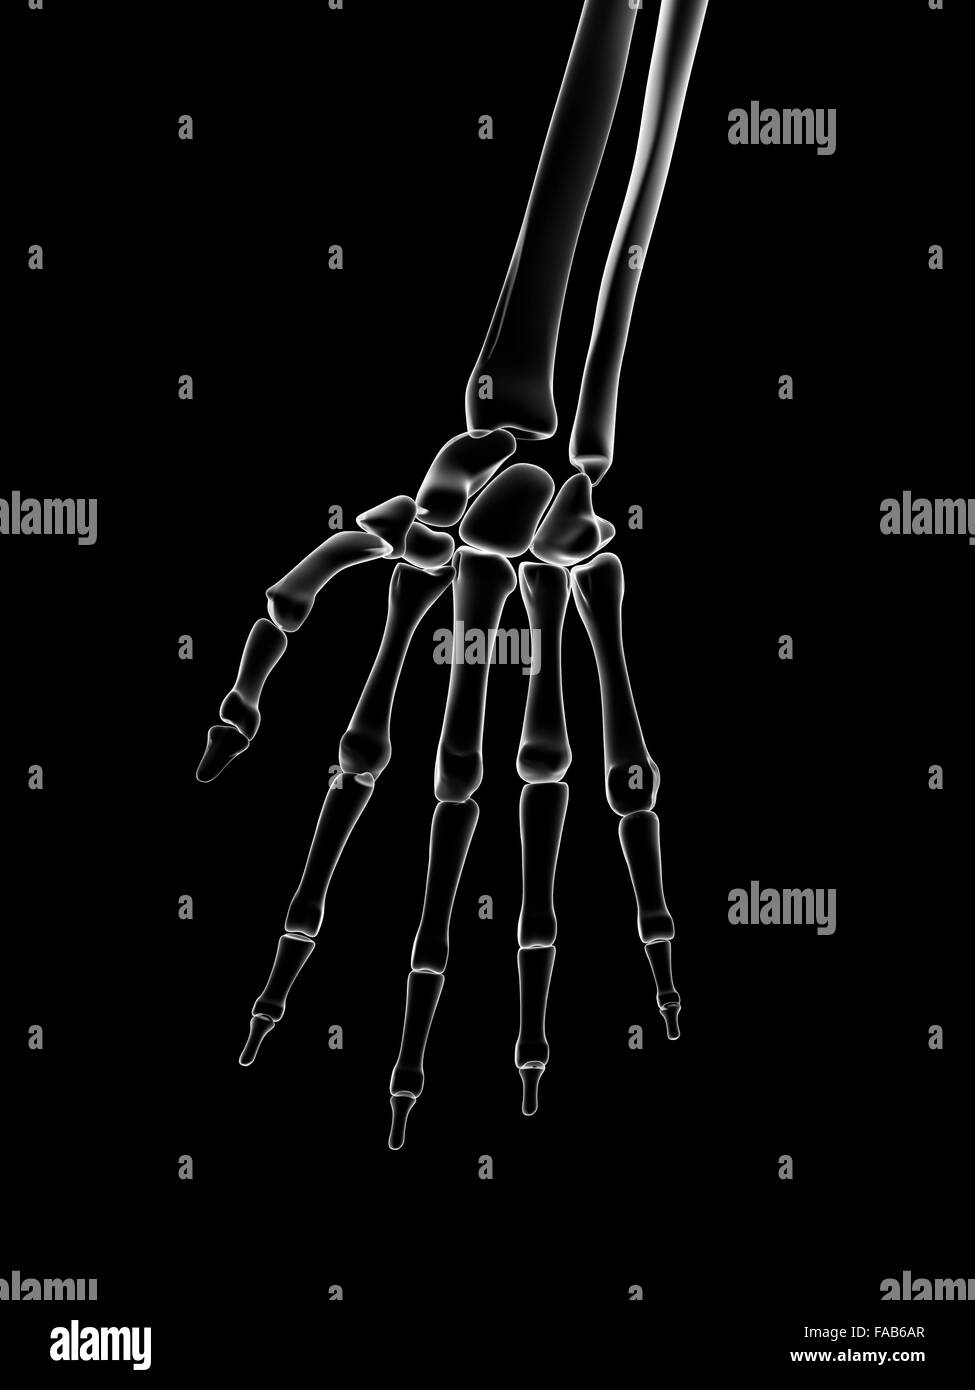

Huesos de la mano humana, equipo de ilustración Fotografía de stock Alamy

Huesos de la mano

Las manos están formadas por más huesos y partes móviles que cualquier otra zona del cuerpo. Si están sanas, estas partes funcionan en conjunto. Realizan una gran cantidad de tareas. Las manos pueden hacer movimientos muy delicados. También pueden hacer tareas que requieren de mucha fuerza. Huesos.. Están localizadas en los extremos de los antebrazos, son prensiles y tienen cinco dedos cada una. A continuación os presentamos las 15 partes de la mano y sus funciones. 1. Los huesos de la mano. La mano humana está compuesta por un total de 27 huesos diferenciados en tres zonas en función de su posición.

Cada dedo tiene tres falanges (distal, media y proximal); solamente el pulgar tiene dos. Huesos metacarpianos. Los cinco huesos que componen la parte media de la mano. Huesos carpianos. Los ocho huesos que forman la muñeca. Los huesos carpianos están conectados a dos huesos del brazo–el hueso cúbito y el hueso radio.. falange: Uno de los huesos de los dígitos. Carpas de la mano izquierda: Hay ocho huesos carpianos en cada muñeca: escafoides, lunados, triquetrales, pisiformes, trapecios, trapecios, capitados y hamates. La mano contiene 27 huesos. Cada una pertenece a una de tres regiones: los carpos, (muñeca), los metacarpianos, (la palma) y las falanges.